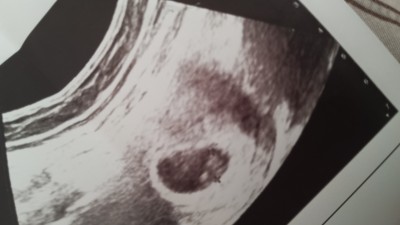

Doktora gittim kal atışını duymak için 6 haftalıken bana ikiz olabileçeğini söyledi  ultrason fotoğraf yükiycem bı bakabilirmisiniz  ultrason da iki tane artı var doktor işaretledi 10 gün sonra belli olur dedi belki ikiz gebelik yaşanlar yardımcı olur

Gebelik haftası 6 hafta

Iki arti bas ve popo ölçümü